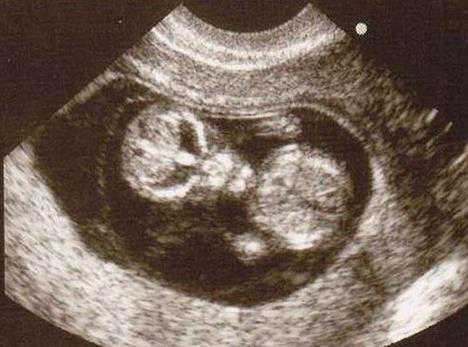

该图中宝宝摇身一变成了“外星人”,难道世上真有“外星人”,到人类投胎了?